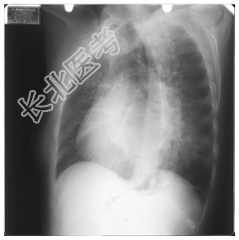

- [材料题] 女,50岁,主诉:胸闷、心悸4个月。听诊:心尖部听到舒张期和收缩期杂音。

- 简答题1、请问该案例诊断是什么?

- 简答题2、请问诊断依据是什么?

- 简答题3、风湿性心脏病临床表现有哪些?